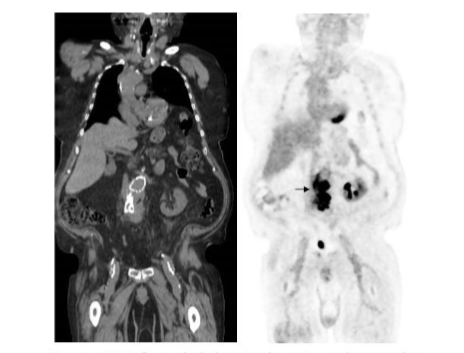

In a brief period of time, ¹⁸F-FDG has become the molecular imaging study of choice for sarcoid, with an overall sensitivity of 89%–100% (Figure 16). It is more sensitive than the ACE and soluble interleukin-2 receptor test. Whole-body imaging facilitates identification of unsuspected sites of disease, guiding patient management⁶⁰,⁶¹.

Figure 16.

There is bilateral upper lung and mediastinal nodal uptake of ¹⁸F-FDG in a patient with active sarcoid.

This test is useful for monitoring treatment response (Figure 17). Decreasing ¹⁸F-FDG lesion avidity after initiating treatment correlates with clinical improvement, while persistent activity is present in non-responders⁶²,⁶³.

Figure 17.

Follow up ¹⁸F-FDG after treatment shows complete resolution of the parenchymal and nodal abnormalities (compare with figure 16).